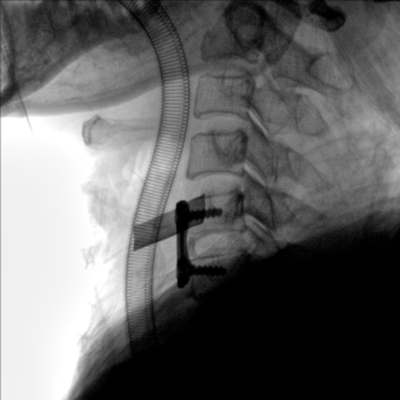

臨床適用科室:骨科、普通外科、矯形外科、創(chuàng)傷外科、泌尿外科、脊柱外科、疼痛外科、消化科、婦科等科室。

大尺寸動態(tài)平板探測器,高DQE、低噪聲、圖像清晰。采用多分辨率圖像增強(qiáng)處理技術(shù),不同部位不同圖像處理算法,滿足客戶多樣化的需求。

多角度自由旋轉(zhuǎn),滿足患者復(fù)雜擺位需求。